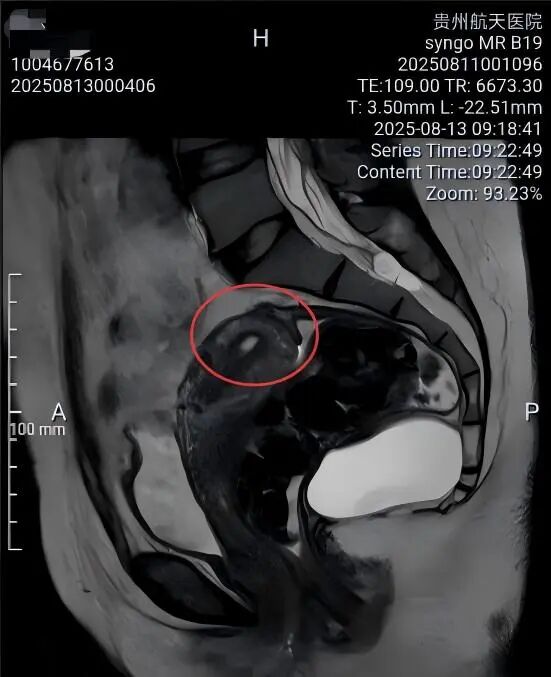

一名女性患者长期受到下腹部坠胀、排便不适等症状困扰,近期发现盆腔内存在肿物,严重影响其生活质量,为寻求进一步诊治,她前往贵州航天医院普外科就诊,经核磁共振(MRI)检查提示:盆腔内直肠与骶骨之间有一个“骶前囊肿”。由于该囊肿位置深,且与周围重要的神经和血管关系密切,若采用传统手术不仅创伤大,还伴随一定的风险。 面对这一棘手难题,普外科立即组织了麻醉科、医学影像科、妇科、重症医学科在内的多学科专家会诊(MDT)。经专家团队详细评估,与患者及家属充分沟通后,为患者制定并成功实施了“腹腔镜下骶前囊肿切除术”。术后恢复良好,不久便康复出院。 【疾病科普|什么是骶前囊肿?】 骶前囊肿,可以理解为生长在骨盆最深处、直肠后方的一个囊性肿物。由于它“躲藏”的位置非常特殊,四周紧邻着控制排便和感觉的重要神经与血管,因此被视为盆腔外科手术中的一个难点。 它可能带来哪些影响? 1.随着囊肿逐渐增大,可能会压迫直肠,引起排便困难或坠胀感。 2.压迫骶神经,可能导致腰骶部或会阴区的酸胀、疼痛。 3.囊肿本身也可能发生感染,形成脓肿,加重不适。 【技术介绍|腹腔镜下骶前囊肿切除术】 对于骶前囊肿这类较深的病灶,腹腔镜下骶前囊肿切除术提供了一种更为微创、便于操作的解决方案。 它是如何进行的? 医生仅通过腹部几个约0.5-1厘米的小孔,其中一个孔放入带高清摄像头的腹腔镜,将盆腔内的景象放大并清晰地投射到屏幕上,如同给了医生一双进入体内的“眼睛”。其他几个小孔则伸入细长的专用手术器械。医生看着屏幕,遥控这些器械,在清晰的视野下精细地分离并完整切除囊肿。 腹腔镜微创手术的特点包括: ▶创伤较小:避免了传统手术的长切口,体表疤痕小。 ▶视野清晰:放大后的图像让医生能更清楚地分辨囊肿与周围重要结构。 ▶操作精准:有助于更完整地切除囊肿,并尽力保护盆腔神经功能。 ▶恢复较快:因手术创伤小,患者术后疼痛感更轻,下床活动早,住院时间也可能缩短。 注:本文旨在进行健康科普,分享医疗案例与科普知识,不能替代任何专业的医疗建议。如有任何健康问题,请务必及时咨询并遵从专业医生的诊疗意见。 贵州航天医院普外科专家简介 高大勇 普外科(肛肠外科)学科带头人、名誉主任,主任医师、教授 临床擅长:对中西医结合诊治肛肠学科各种常见病、多发病及疑难杂症等具有丰富的临床经验。 原遵义市第一人民医院(遵义医科大学第三附属医院)、遵义市中医院肛肠科主任。中华中医药学会肛肠分会常委,全国中医肛肠学科名专家,中国健康促进与教育协会肛肠分会常委,中国康复医学会肛肠疾病康复专业委员会常委,中国民间中医医药研究开发协会肛肠分会副秘书长,中国医师协会中西医结合肛肠医师专业委员会常委,国家二级心理咨询师,贵州省第一批中医名医工作指导老师,遵义市名中医,遵义市肛肠学会会长,遵义市肛肠质控中心名誉主任,遵义市中西医结合学会名誉会长,遵义市健康科普专家,原贵州省中西医结合学会肛肠分会副主任委员、贵州省中医肛肠质控中心副主任、遵义市医学会医疗鉴定委员会专家、遵义市卫生系列高级评委。发表论文30余篇,主编和参编医学著作5本,主持省级科研课题2项、市级科研课题2项、院级科研课题1项。 梁 跃 普外科党支部书记、主任,主任医师 临床擅长:对普外科各类肿瘤手术具有丰富的临床经验。 毕业于遵义医学院,遵义市医学会小儿外科学分会常务委员,遵义市肛肠协会理事,遵义市医学会核医学分会(第二届)委员会委员;荣获第三期“黔医人才计划”优秀学员称号;主持市级课题1项,完成省级课题1项,在国内各类刊物上发表论文10余篇。 钱科洪 民盟盟员,普外科副主任医师 临床擅长:从事普外科临床工作30余年,对各类普外科疾病的诊治、乳腺、甲状腺、胃十二指肠、结直肠等疾病及疑难杂症具有丰富的临床经验。 毕业于遵义医学院临床医疗系,2009年前往中山大学附属第一医院微创外科进修学习,在国内各专业期刊发表论文数篇。 贵州航天医院普外科简介 基本情况 贵州航天医院普外科成立于1968年,前身属于原航天部O61基地3417医院外一科,1998年3417医院、3427医院合并后更名为普外科,下设胃肠外科、肛肠外科2个亚专业科室,拥有在全市较为先进的专科设备和技术,是中国疝病专科联盟单位,贵州医科大学附属医院胃肠外科专科联盟单位。开放床位40张,配备医护人员21人。 专科特色 普外科致力于胃肠及肛肠疾病的外科临床诊治及科研,以腹腔镜微创外科技术为本,形成以快速康复治疗胃肿瘤、结直肠肿瘤、小肠肿瘤、直肠脱垂、肥胖病、急腹症、各类疝、痔、瘘等专科特色,同时注重胃肠疾病尤其是结直肠恶性肿瘤的基础研究和临床转化研究,总体诊断和治疗水平在区域同级医院居于领先水平。 开展手术:腹腔镜下胃癌根治术,腹腔镜下袖状胃切除术,腹腔镜下胃肠道间质瘤切除术,腹腔镜下结、直肠癌根治术,胃癌、结直肠癌的精准治疗,腹腔镜下小儿疝气、成人疝修补术,腹腔镜下阑尾手术,内痔的硬化注射治疗及痔疮的微创治疗:ATH、PPH、TST,直肠脱垂的各种手术治疗,难治性伤口VSD技术,鼻胃肠管、肠梗阻导管置入术,肛肠术后间歇性导尿技术,并引进了中医适宜技术,也为各种化疗患者提供输液港安装,提高患者就医体验。 腹腔镜下腹股沟疝 无张力修补术 腹股沟疝里金斯坦 (Lichtenstein)手术 PPH微创术治疗环状混合痔 黏连性或炎性肠梗阻-肠梗阻导管 腹腔镜袖状胃切除 腹腔镜阑尾切除术 腹腔镜阑尾肿瘤切除术 腹腔镜下结肠癌根治术 诊疗范围 胃肿瘤、结直肠肿瘤、小肠肿瘤、肥胖症、各类急腹症、腹部外伤、腹壁疝、便秘、直肠脱垂、痔疮、肛瘘、肛裂等胃肠、肛肠外科疾病。 END